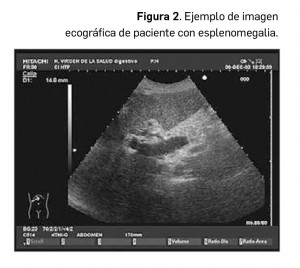

En nuestro medio, la hipertensión portal es la causa más frecuente de aumento de tamaño del bazo o esplenomegalia (Figura 2), recomendándose un estudio exhaustivo para descartar la existencia de circulación colateral y signos de cirrosis hepática, en casos de detección casual de esplenomegalia en cualquier estudio rutinario.